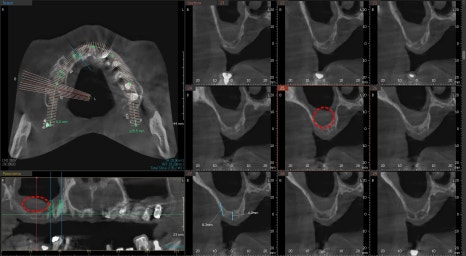

이비인후과 수술 후 경과

이비인후과에서 비염 수술을 하신 후

3달 정도가 지난 사진입니다.

과거에 상악동을 채우고 있던 희뿌옇던 염증이 사라졌지만

만성 염증에 의해 점막이 부어있습니다만

이 정도는 상악동거상술을 하기에는 방해요소는 아닙니다.

상기 환자는 남아있는 잔존골의 양이 너무 적기 때문에

측면에서 접근하는 측방접근법을 이용하여

치조골 이식술과 동시에 임플란트 수술을 했습니다.

상악의 전체 임플란트 수술

위턱뼈의 치아들이 발치를 요하는 정도의

동요도를 갖고 있었고, 주변 뼈들이 얇기 때문에

전체 발치를 결정하고 기존 견고한 뼈 주변에

치조골이식술을 동반한 수술을 진행했습니다.